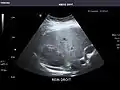

Left kidney

Kidneys: Right and left kidneys measure 11.5 cm and 12 cm in length respectively. No hydronephrosis. Small left lower pole kidney cyst.